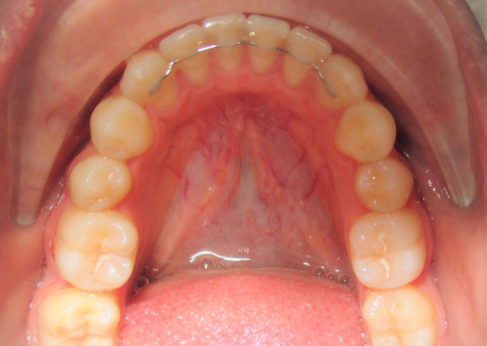

Permanent Retainers

Permanent retainers are usually made of thin gold or stainless steel wires and are cemented behind front teeth. They are mostly used to hold the lower front six teeth although they can be used in the upper teeth in certain cases as well. Permanent retainers are safe, easy to maintain and very effective in preventing tooth shifting (relapse). For all of these reasons, we recommend using lower permanent retainers on almost all of our cases.